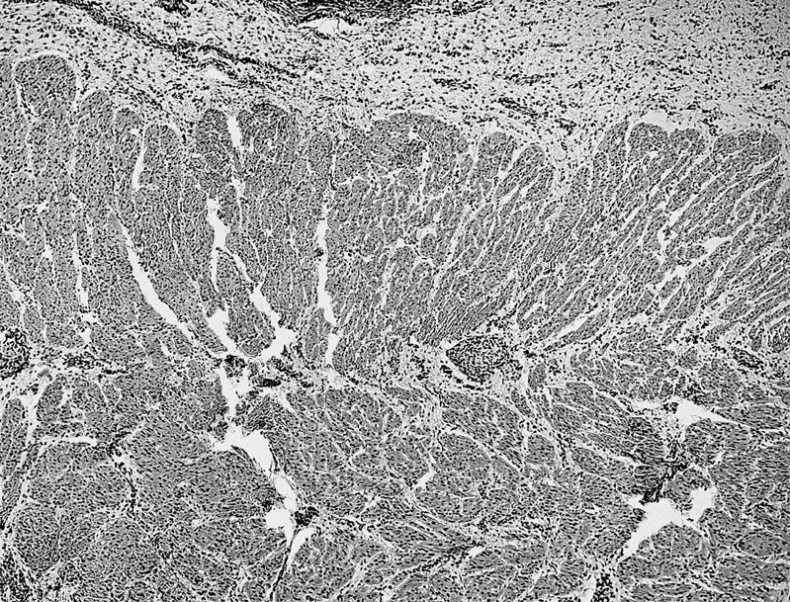

Поперечно-полосатая мышечная ткань делится на скелетную и сердечную.

Поперечно-полосатая сердечная мышечная ткань

Клетки поперечно-полосатой сердечной мышечной ткани, называемые «кардиомиоцитами», имеют прямоугольную форму и относительно небольшие размеры — до 120 мкм в длину и 20 мкм в ширину. Кардиомиоциты обычно имеют одно ядро. Особенность их в том, что они связаны друг с другом при помощи особых вставочных дисков. Благодаря этой связи, электрический импульс, вызывающий сокращение, имеет возможность быстро распространяться по большому участку мышечной ткани.